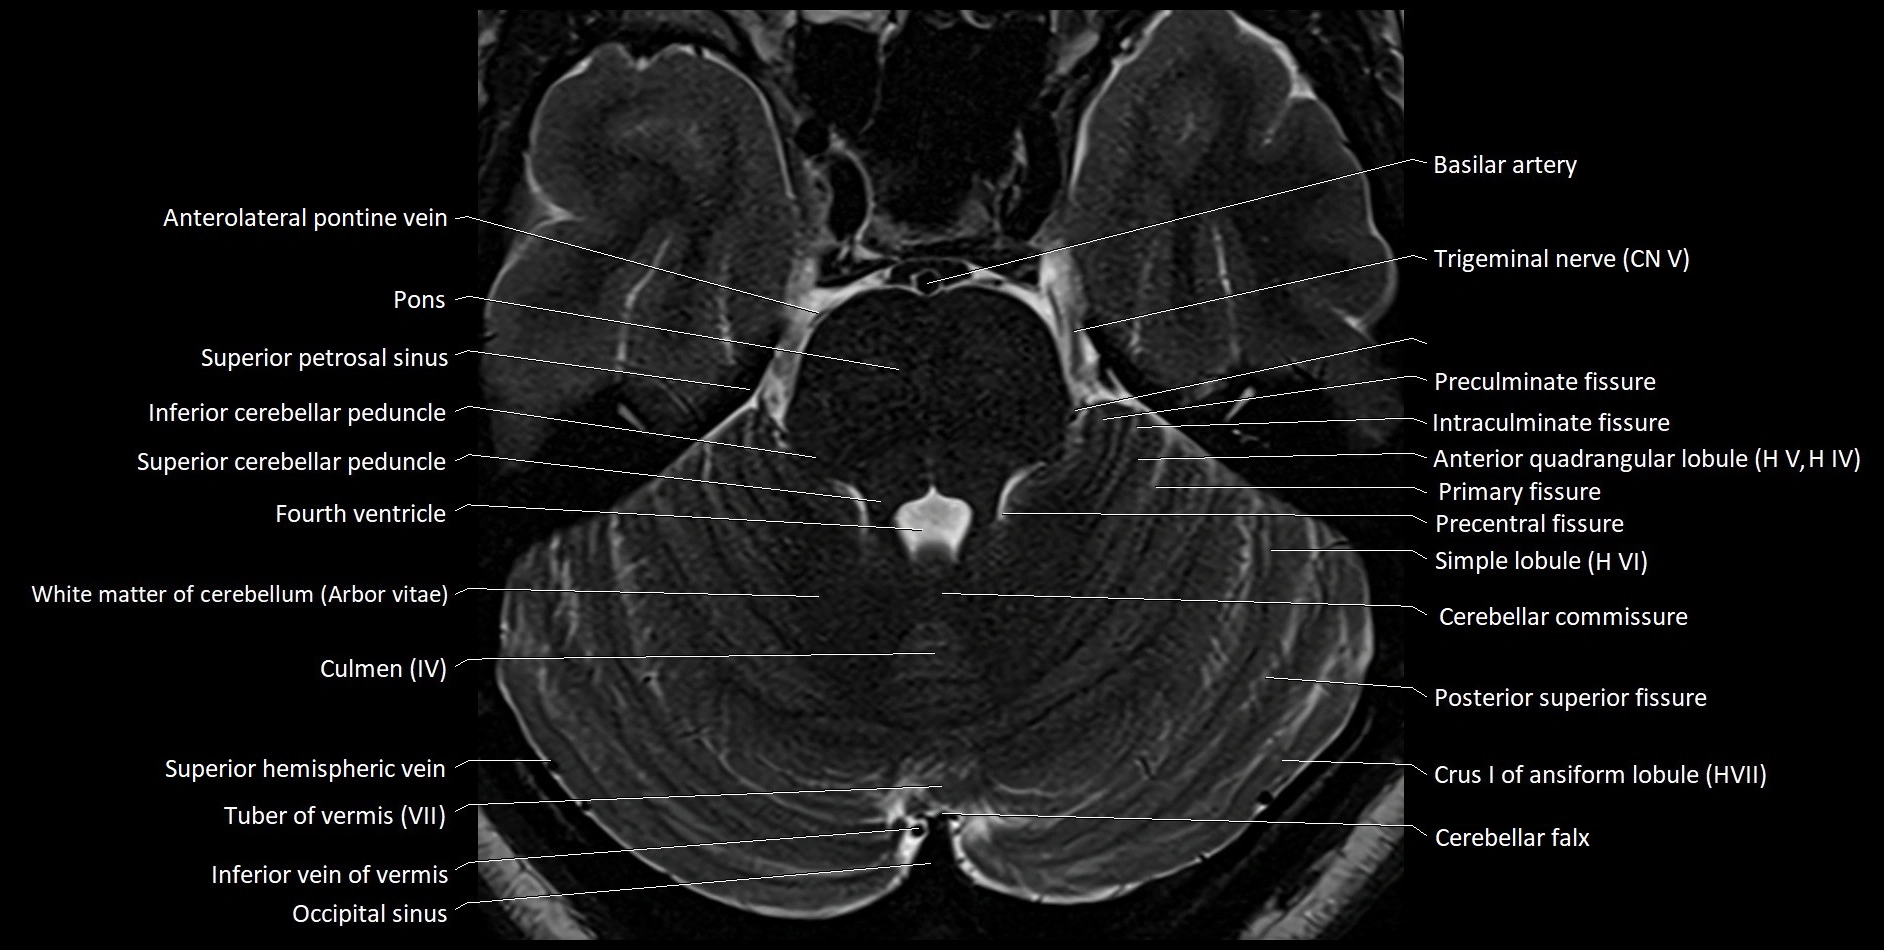

MRI images